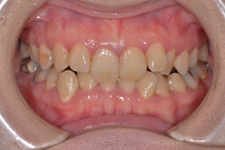

上下前歯のガタガタの症例です。ガタガタしている所は歯ブラシがとどかないので、茶色く着色しています。重なっている所は虫歯になっていることが、ほとんどです。

ガタガタの量が多く、物理的に顎の骨に入りきらないため、上下左右の前から4番目の歯(第一小臼歯)を抜いて、治療しました。抜かずに治療した場合、歯列の円周が広がり口元が突出してしまうため、抜歯をご選択されました。矯正後は歯磨きもし易く、歯の色も一緒にきれいになっています。